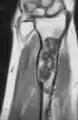

Magnetic resonance imaging (MRI), ultrasound, and scintigraphy are generally not practical for diagnostic purposes. X-rays are not as effective in the monitoring or evaluation of enchondromas due to frequent localized changes also sometimes due to the large number of enchondromas. MRI can sometimes however be used to monitor and evaluate symptomatic lesions in the case of potential malignant transformations.

MRI showing enchondromas localized in the lower part of the radius of a 37-year-old patient affected with Ollier disease

MRI showing enchondromas localized in the lower part of the radius of a 37-year-old patient affected with Ollier disease.